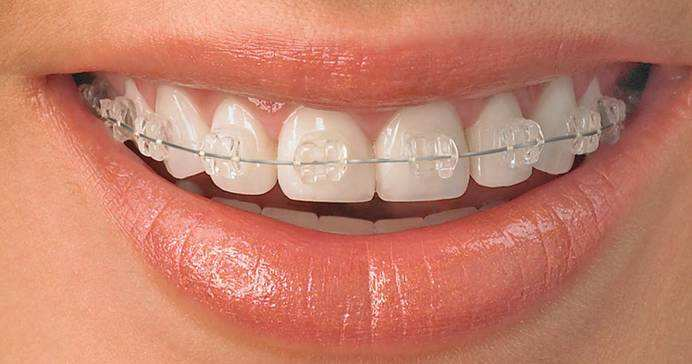

陶瓷托槽

优点:托槽近透明色,美观

缺点:价格较高